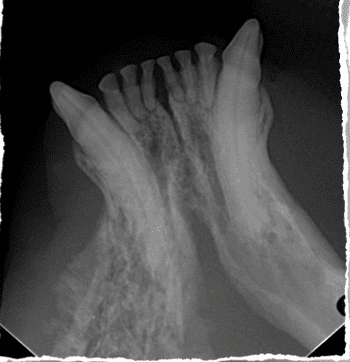

Squamous cell carcinoma is commonly mistaken for periodontal disease in many feline cases. It is locally invasive and tends to invade bone rapidly. Diagnosis is achieved through a combination of an anesthetized oral exam, dental imaging, and biopsy. Advanced dental imaging such as cone-beam CT or conventional CT is strongly encouraged and warranted for appropriate surgical planning.

nvades the nearby bone. A common location is under the tongue, making identification and treatment challenging. Although metastasis and lymph node involvement is not common in feline oral squamous cell carcinoma, it generally carries a poor prognosis in cats due to the primary tumor’s locally aggressive biologic behavior. Local disease progression interferes with food and water consumption and reduces the pet’s quality of life. Many cats hide illness well, and the discovery of a tumor is often not realized until it has reached an advanced stage.